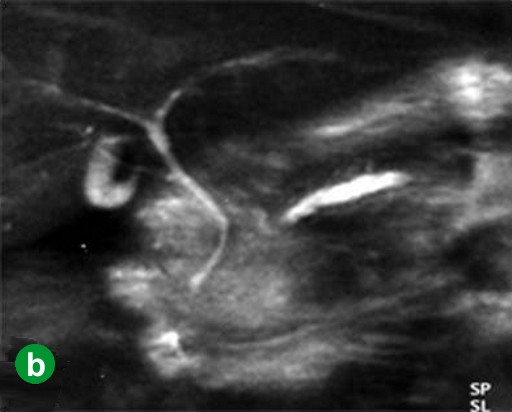

In January 2008, the patient complained of hydrodipsia and polyuria, and was diagnosed with diabetes mellitus. An abdominal CT scan revealed a 3 cm tumor in the tail of the pancreas (Figure 2a). Tumor marker (CEA and carbohydrate antigen (CA) 19-9) levels were within the reference limits, and had been throughout previous monitoring. Recurrence was confirmed using FDG-PET at 84 months after the initial operation. The FDG-PET hot spot corresponded with the tumor location shown by the CT scan (Figure 2b). The patient underwent surgery in June 2008. An intra-operative pathological examination indicated an adenocarcinoma of the remnant pancreas. A remnant distal pancreatectomy with a splenectomy was performed. The histopathological findings for the second neoplasm were similar to those of the initial lesion (Figure 2c). Carcinoma cells had invaded vessels, lymph ducts and neurons, and there were lymph node metastases (T3N1M0; R0; pathological stage: IIB). The patient was alive at 10 months after the second operation without any recurrence.

Figure 2. Case#1: second operation. a. A tumor approximately 3 cm in diameter was detected in the pancreatic tail on abdominal CT. b. A hot spot in FDG-PET corresponded to the tumor site on CT. c. A well- or moderately-differentiated tubular adenocarcinoma similar to the initial pancreatic cancer was detected. Mild atypical cells with a slightly swollen nucleus formed an irregular ductal structure and invaded the parenchyma. (H&E stain, x100). |